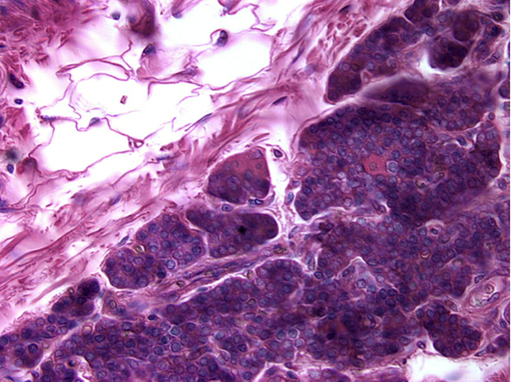

The above photos show higher magnifications of the pars distalis. You should be able to distinguish acidophils and basophils in this and your slide. To do this, look at the color of the red blood cells in the vessels (V). Then, match the color to cells in the pituitary. Those are the acidophils (A). Cells that are more "purple", or blue are the basophils (B). Cells that have hardly any color are the chromophobes. There are few true chromophobes since at the electron microscopic level most pituitary cells have the granules that are characteristic of a particular cell type. They are simply degranulated acidophils or basophils.